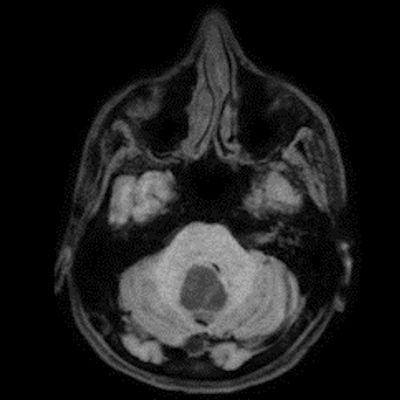

- B) Beyin MRG incelemesinde; 4. ventriküle bası etkisi oluşturan yaklaşık 3.5 cm boyutta, T2A hiperintens T1A hipointens kistik komponent (oklar) ve posteriorunda T1 ve T2A serilerde parankim ile izointens, içerisinde flow void alanların (oklar) izlendiği, post kontrast görüntülerde yoğun kontrast tutulumu gösteren mural nodül (oklar) barındıran düzgün sınırlı lezyon izlenmektedir.

- Kistik komponent: T1A hipointens, T2A hiperintens

- Mural nodül: T1A izo-hipointens, T2A orta derecede hiperintens olabilir.

- Kontrastlı incelemelerde mural nodül belirgin ve yoğun kontrast tutulumu gösterir. Ancak kist duvarında genellikle kontrastlanma beklenmez.

- T1 ve T2A görüntülerde flow voidler sıktır.